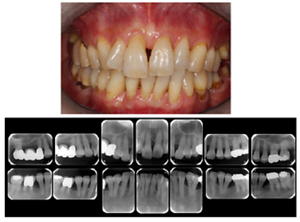

図8 長期メインテナンスの実際

1999年初診。年齢32歳 女性、“はぐきが腫れる”という主訴で来院されました。若い年齢にもかかわらず重度歯周炎にすでに罹患をしていました。

治療後21年。右上第1大臼歯は治療時に抜歯となってしまいましたが、治療完了後は定期メインテナンスを継続し、歯周組織は安定、一本の歯も失わずに現在まで経過しています。